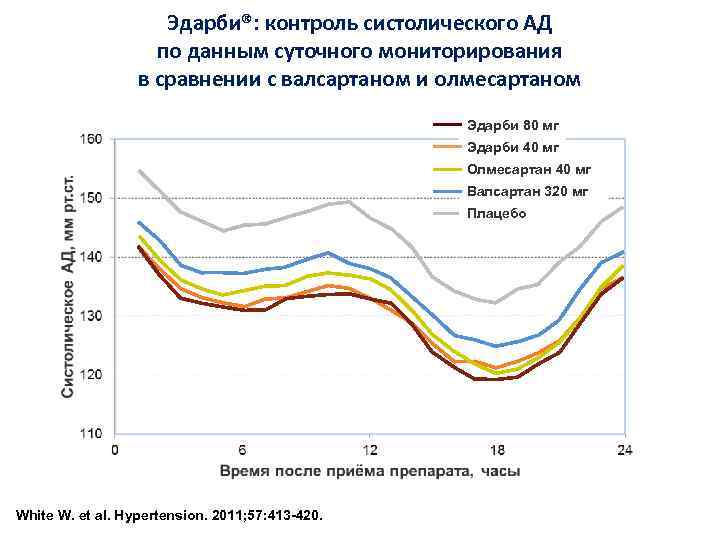

Эдарби®: контроль систолического АД по данным суточного мониторирования в сравнении с валсартаном и олмесартаном Эдарби 80 мг Эдарби 40 мг Олмесартан 40 мг Валсартан 320 мг Плацебо White W. et al. Hypertension. 2011; 57: 413 -420.

Эдарби®: контроль систолического АД по данным суточного мониторирования в сравнении с валсартаном и олмесартаном Эдарби 80 мг Эдарби 40 мг Олмесартан 40 мг Валсартан 320 мг Плацебо White W. et al. Hypertension. 2011; 57: 413 -420.